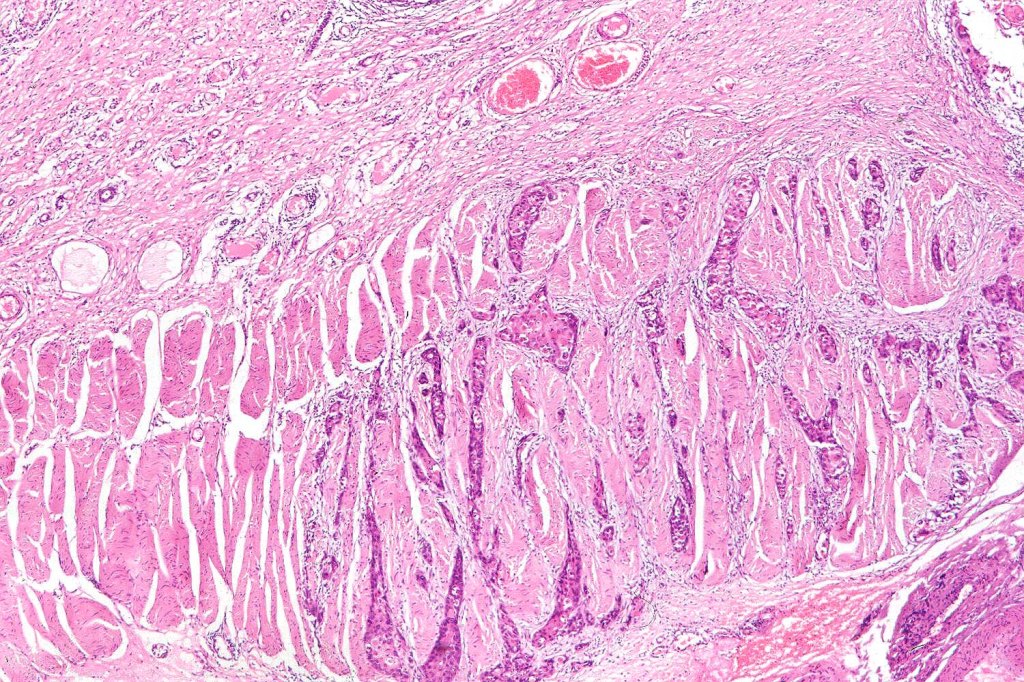

•Variants include verrucous, acantholytic, follicular, clear cell, spindle cell, metaplastic (squamous carcinosarcoma, desmoplastic, pseudovascular & keratoacanthoma (see separate bogs)

•Generally, an infiltrative lower border but exceptionally, may be pushing

. Presence of desmosomes, individual cell keratinization, keratin pearls, keratocysts